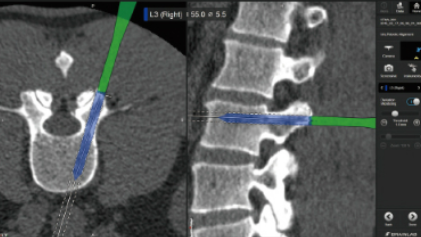

9月7日,横滨市立大学附属医院在横滨市政记者会上发布,成功于2022年6月实施日本首例利用手术支援机械臂(Cirq机械手臂系统)进行颅内电极放置、立体脑电图监测手术。(stereotactic electroencephalography:SEEG) 为治疗难治性癫痫患者需在大脑表面或内部放入电极,来监测查找大脑皮质神经元异常放电的部位(癫痫病灶),病灶部位会直接或间接导致痫性放电导致癫痫发作,一般治疗手法为将该部分切除。与传统手术相比SEEG手术并不需要直接开颅,并且与以往使用片状电极放置相比,身体负担更小。另外,因无需开颅,所以大脑深度区域的癫痫病灶和脑神经电网的监测不受开颅范围的限制,可以更有效地探索病灶点。 据悉,该机器手臂具有接近人类手臂、手、手指的可动性模块,拥有电磁保持和触摸传感器功能的7轴机械臂,同时在应用过程中,还可以通过前端具有校准模块4轴机械臂进行精确调整,并通过定位软件提供直观的可视化指导。